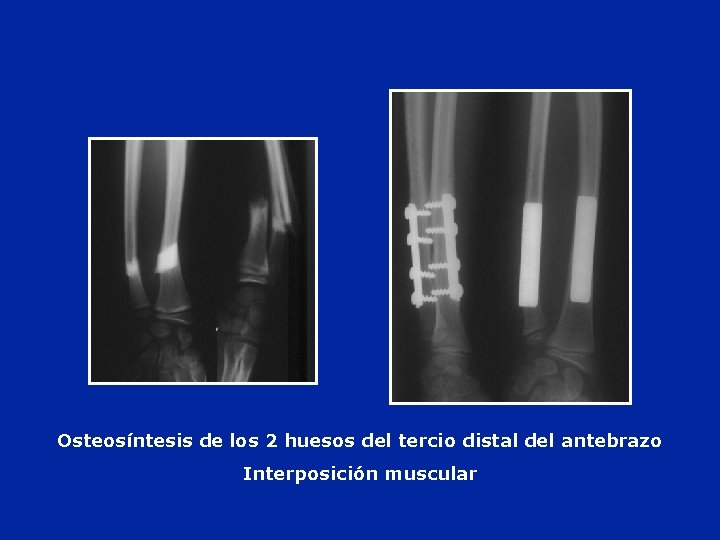

Desplazamiento Osteosíntesis por medio de placas y tornillos

Osteosíntesis de los 2 huesos del tercio distal del antebrazo Interposición muscular